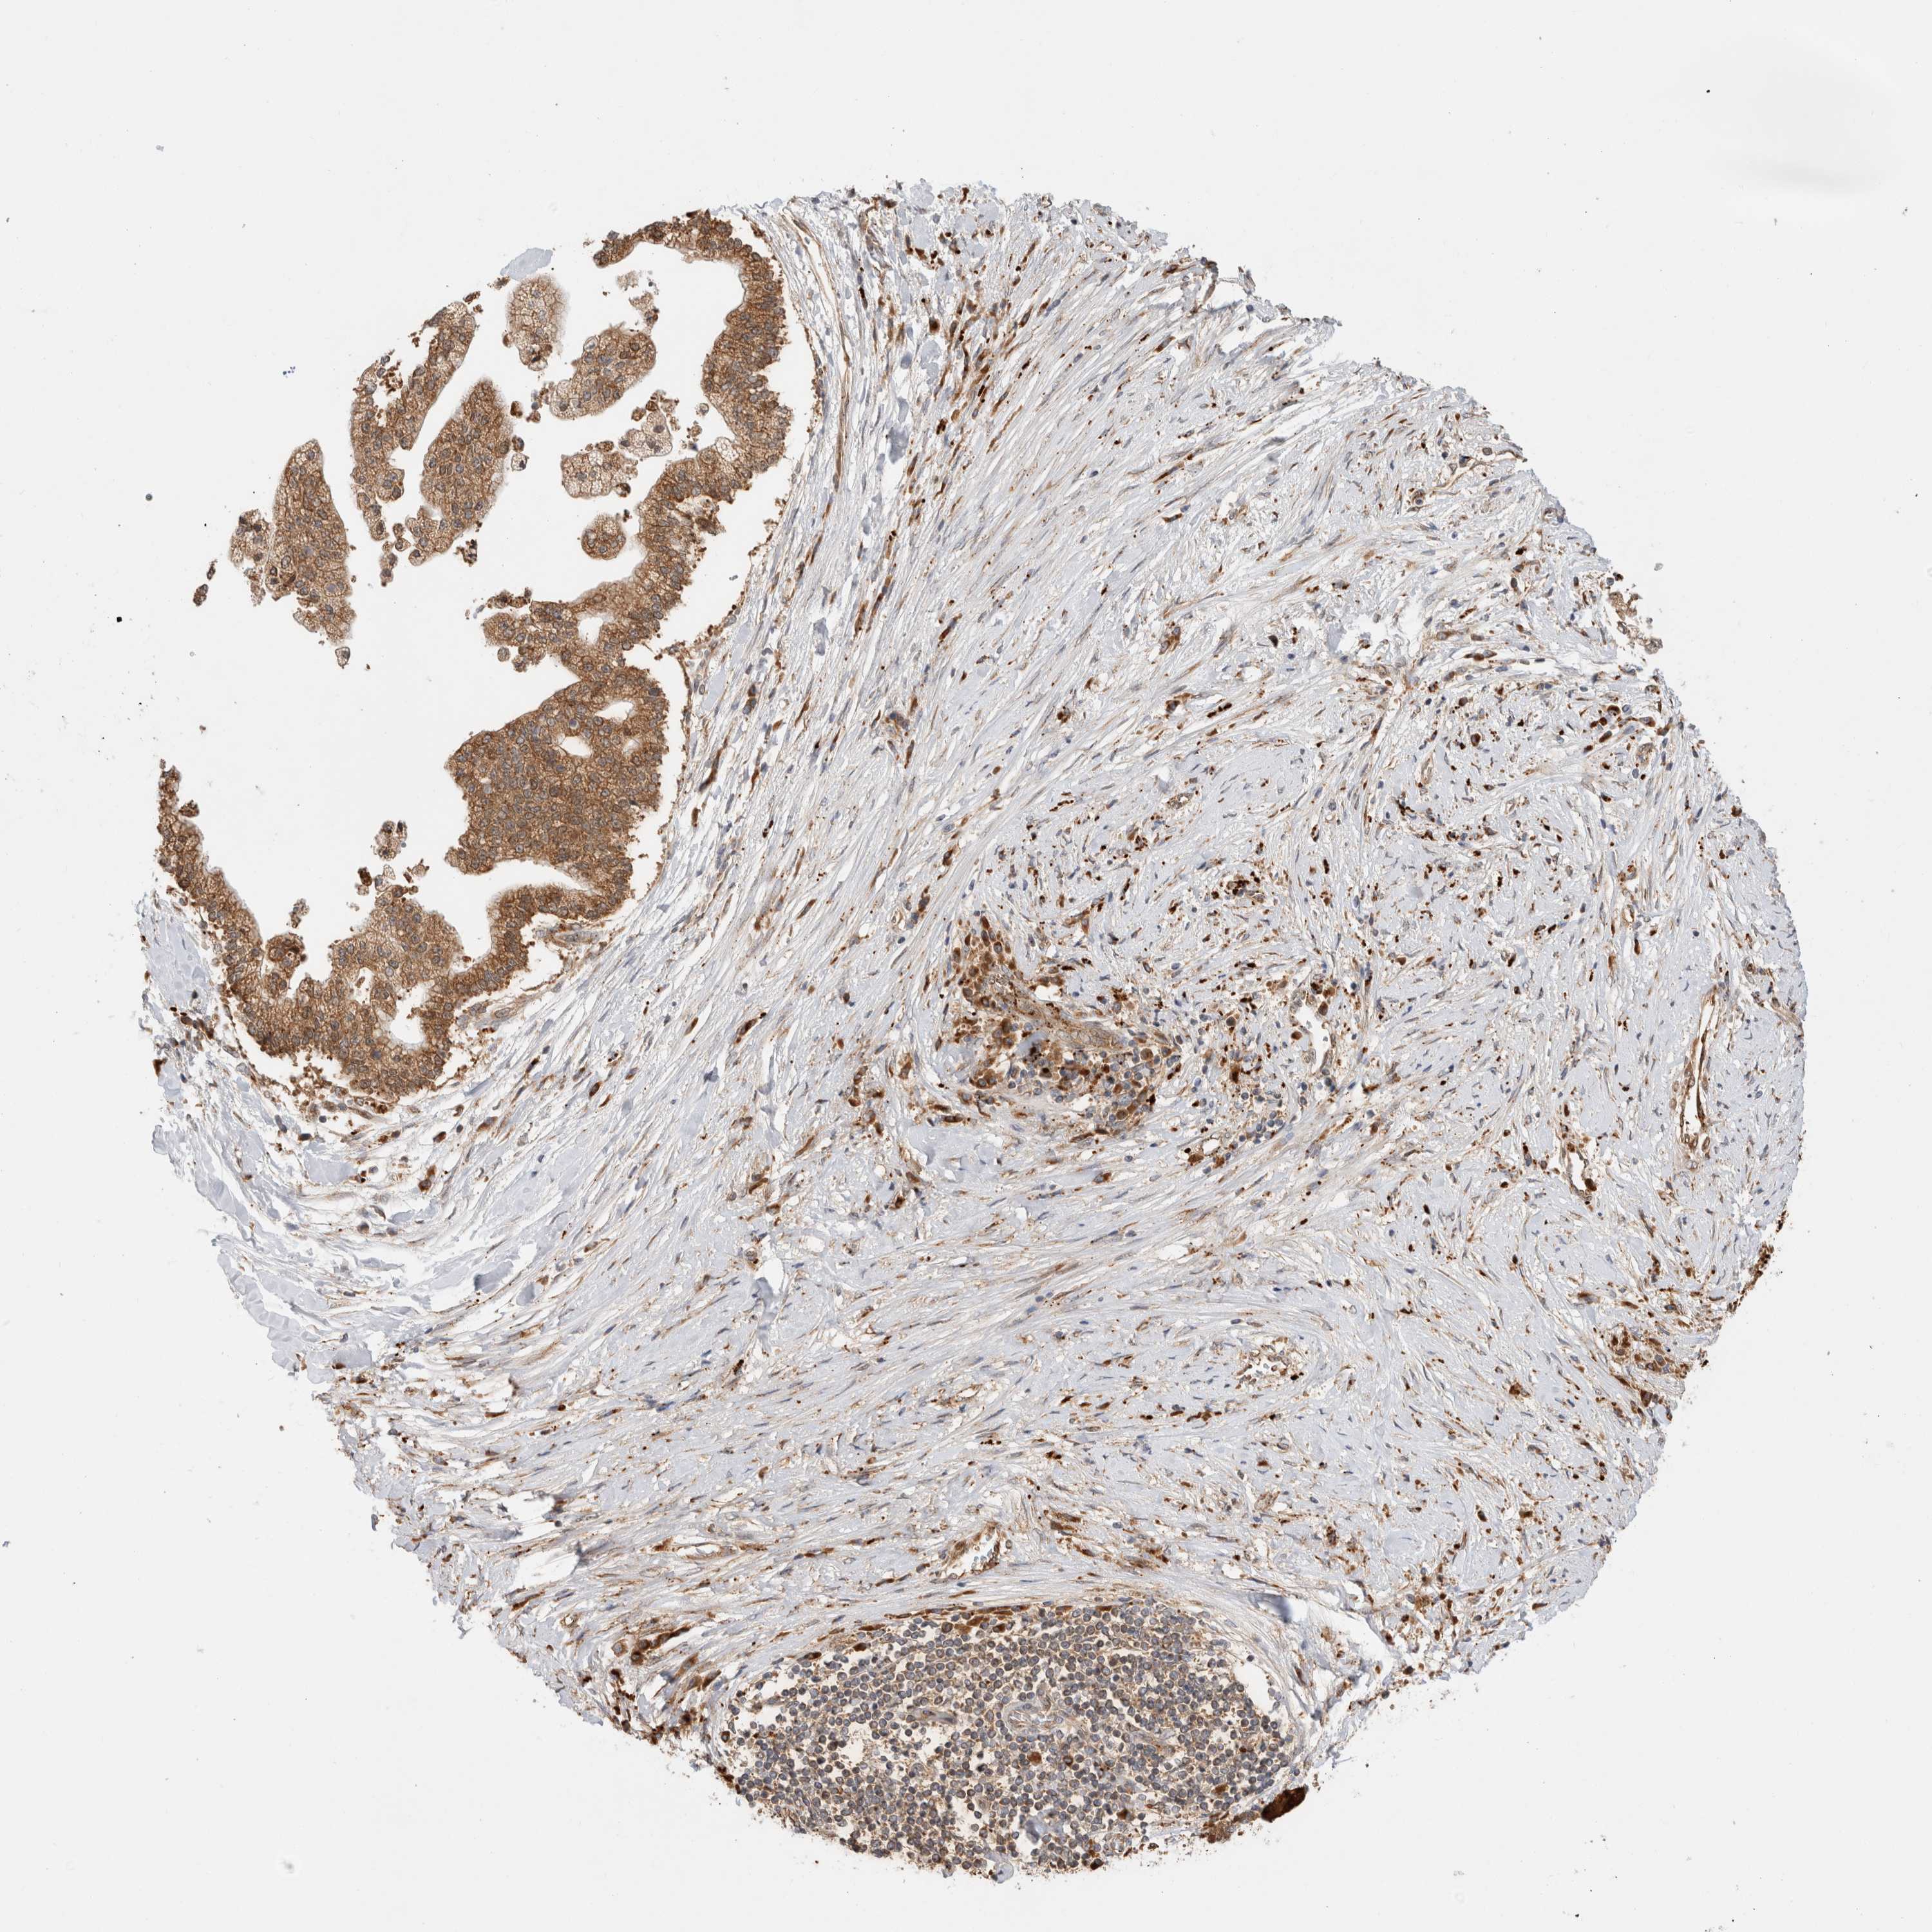

LIVER CANCER - Protein expressioni

A mouse-over function shows sample information and annotation data. Click on an image to view it in a full screen mode. Samples can be filtered based on level of antibody staining by selecting one or several of the following categories: high, medium, low and not detected. The assay and annotation is described here.

Note that samples used for immunohistochemistry by the Human Protein Atlas do not correspond to samples in the TCGA dataset.

Antibody stainingi

Antibody staining in the annotated cell types in the current human tissue is reported as not detected, low, medium, or high, based on conventional immunohistochemistry profiling in selected tissues. This score is based on the combination of the staining intensity and fraction of stained cells.

Each image is clickable and will lead to virtual microscopy that enables deeper exploration of all samples and also displays staining intensity scores, fraction scores and subcellular localization as well as patient and tissue information for each sample.

Antibody HPA019231

Antibody HPA026693

Staining

High

Medium

Low

Not detected

Intensity

Strong

Moderate

Weak

Negative

Quantity

>75%

75%-25%

<25%

None

Location

Nuclear

Cytoplasmic/membranous

Cytoplasmic/membranous,nuclear

Cholangiocarcinoma

Carcinoma, Hepatocellular, NOS